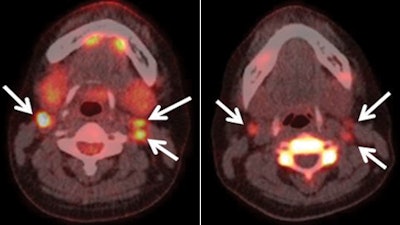

In a face-off of two PET radiopharmaceuticals, FDG-PET/CT outperformed F-18 fluorothymidine (FLT) PET/CT in the diagnosis of postoperative thyroid cancer lymph-node and distant metastases, making the hybrid modality more suitable for examining disease recurrence, according to a study in the June issue of Radiology.

Japanese researchers found that FDG-PET had greater sensitivity, specificity, and accuracy among 20 patients and produced fewer false positives in cervical lymph nodes than FLT-PET.

The scans revealed that 19 patients had papillary carcinoma and one patient had follicular carcinoma. Of the 20 patients, 13 (65%) had concordant uptake of FDG and FLT and seven (35%) had discordant uptake.

FDG outperforms FLT

Patient-based analysis revealed that FDG-PET/CT achieved sensitivity of 92% (12/13 patients), compared with 69% (9/13 patients) for FLT-PET/CT. Specificity was 86% (6/7 patients) with FDG, compared with 29% (2/7 patients) for FLT. FDG had an accuracy of 90% (18/20 patients), compared with 55% for FLT (11/20 patients).